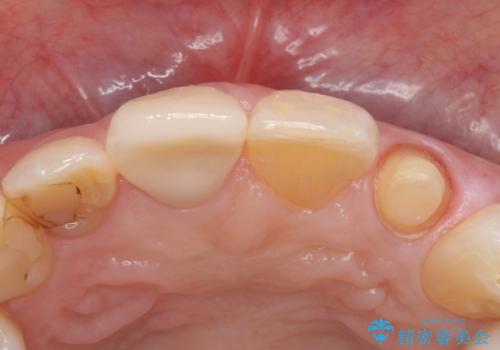

前歯を綺麗にしたい。 ジルコニアクラウンでの修復

- 継ぎ接ぎになった前歯を綺麗にしたいとのことで来院されました。

継ぎ目のないクラウンで修復処置していきます。

精度の良い被せ物を装着することで、違和感のない自然な見た目を獲得することができます。